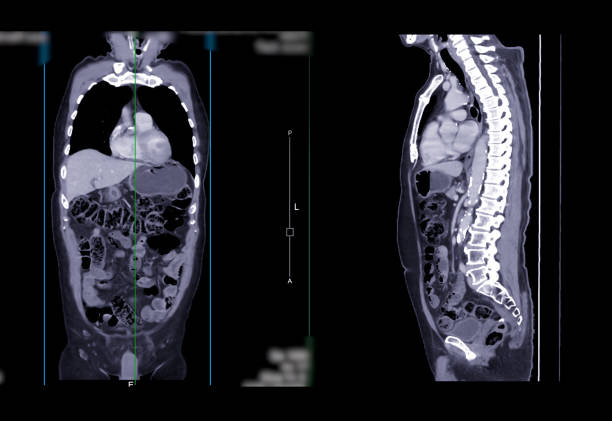

역류성 식도염

역류성 식도염은 위산이 식도로 역류하여 식도의 염증을 일으키는 질환입니다. 이러한 역류는 일시적으로 발생하는 경우도 있지만, 만성적으로 발생하는 경우도 있습니다. 이러한 경우, 역류성 식도염으로 인해 식도에 염증이 생기고 식도의 내막이 손상되면서, 목이 간질간질하고 마른 기침이 나타날 수 있습니다.

식도는 기본적으로 위로부터 내려오는 음식물을 소화시키기 위한 파이프 역할을 합니다. 그러나 역류성 식도염이 발생하면, 위산과 소화액이 역류하여 식도를 자극하게 되면서 염증이 생기고 손상됩니다. 이렇게 손상된 식도는 보호 기능이 약화되어 목이 간질간질하고 마른 기침이 나타나게 됩니다.

또한, 역류성 식도염은 식도와 관련된 다른 증상도 일으킬 수 있습니다. 이러한 증상으로는 가슴통증, 속쓰림, 구역질, 식욕부진 등이 있습니다. 역류성 식도염은 일상적인 식습관 개선과 함께 약물치료와 수술치료 등 다양한 치료방법이 있으며, 치료하지 않으면 식도가 악화되어 식도암 등 심각한 합병증을 유발할 수 있으므로 조기 진단과 적절한 치료가 필요합니다.